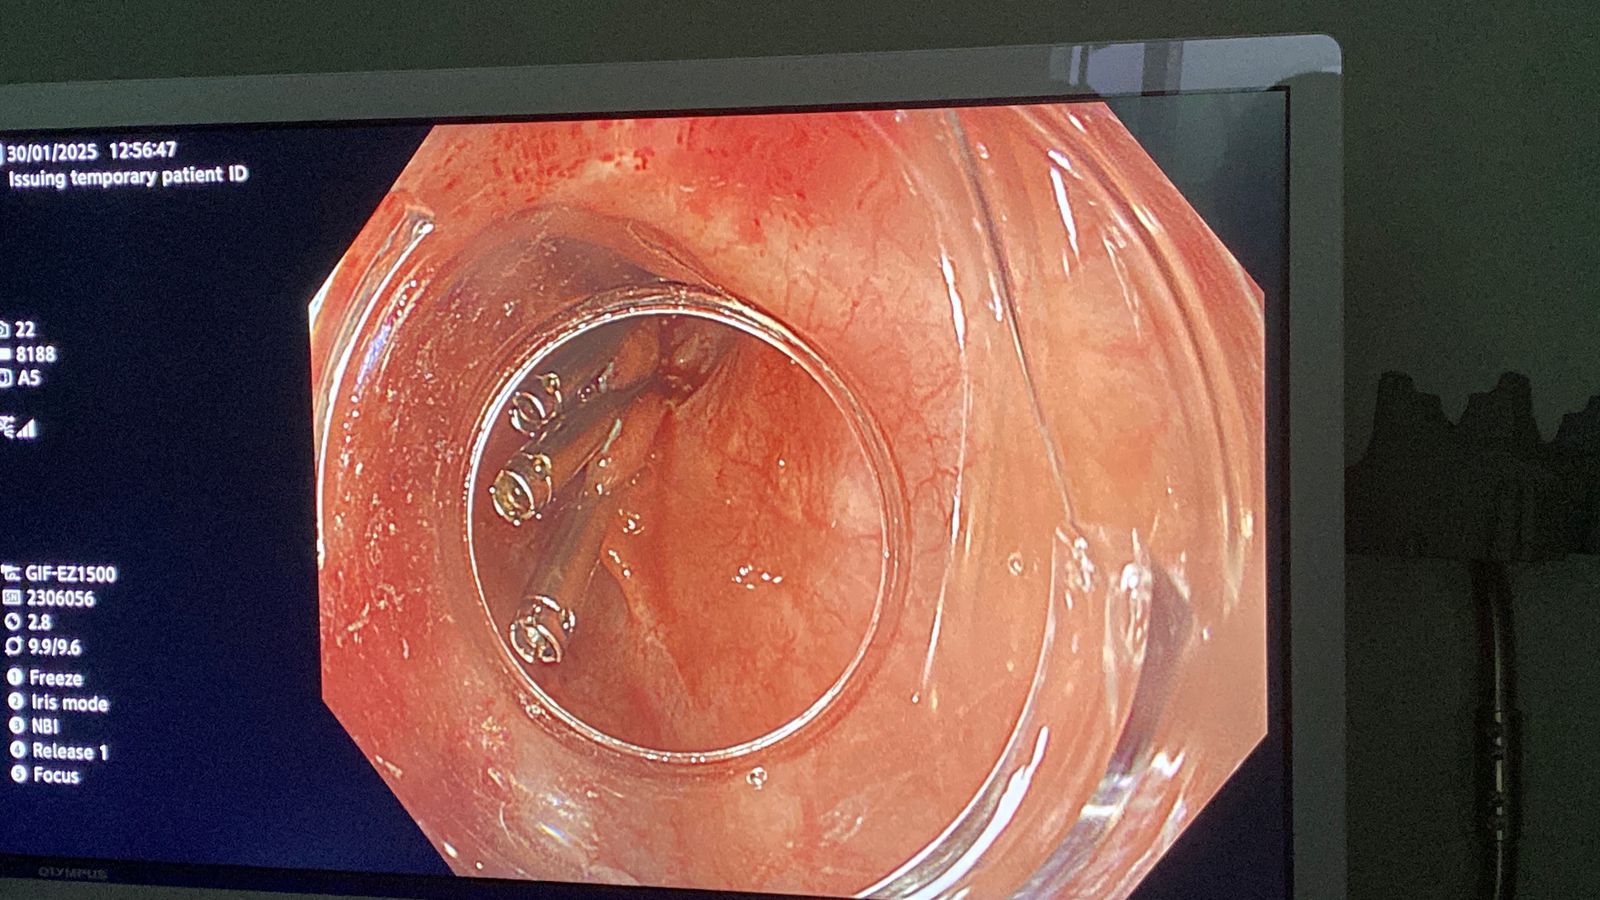

نجحت وحدة المناظير بكلية الطب جامعة حلوان، في إجراء أول عملية من نوعها باستخدام منظار الموجات فوق الصوتية لتشخيص واستئصال ورم بالمريء في جلسة واحدة، دون الحاجة لإجراء فتحات جراحية، وذلك بمستشفى بدر الجامعي.

وأكدت أن تمت العملية في غضون 30 دقيقة باستخدام تقنية مناظير الفراغ الثالث، حيث تم تحديد نوع الورم ومكانه وحجمه ومنشئه عبر منظار الموجات فوق الصوتية، ثم استئصاله مباشرة في نفس الجلسة. وتميزت العملية بتوفير الوقت على المريضة وتجنيبها مخاطر التخدير المتكرر، حيث تم خروجها من المستشفى خلال 24 ساعة في حالة صحية ممتازة دون أي مضاعفات.

وأجريت العملية تحت إشراف الدكتور شريف البحيري، مدرس الباطنة العامة بكلية الطب واستشاري المناظير التداخلية ومناظير الفراغ الثالث، والذي تلقى تدريبًا متخصصًا على هذه التقنية المتقدمة في جامعة كاتب أتاتورك بتركيا خلال مهمة علمية من جامعة حلوان.